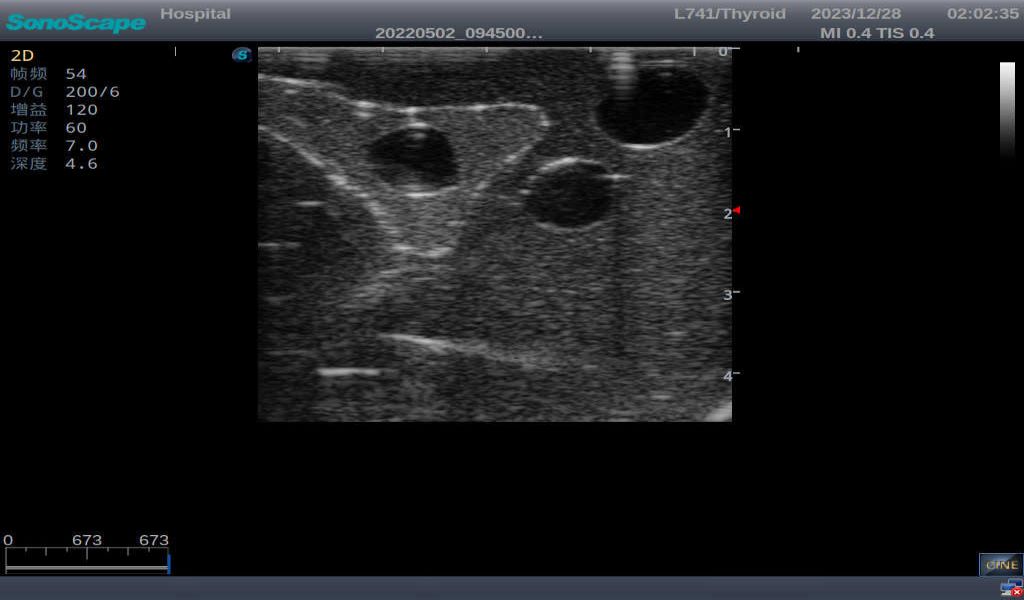

3) It comes with four (4) thyroid modules and can show five (5) ultrasonic images: normal thyroid, thyroid adenoma, thyroid cancer, nodular goiter, thyroid cyst

Thyroid cyst, which fluid area, dark and echo-free area can be seen

2) Ultrasonically realistic materials at neck & various types of real ultrasonic machines in clinical available, developing realistic imaging like common carotid artery, internal jugular vein, trachea, thyroid cartilage, cricoid cartilage, lobes of thyroid gland and isthmus